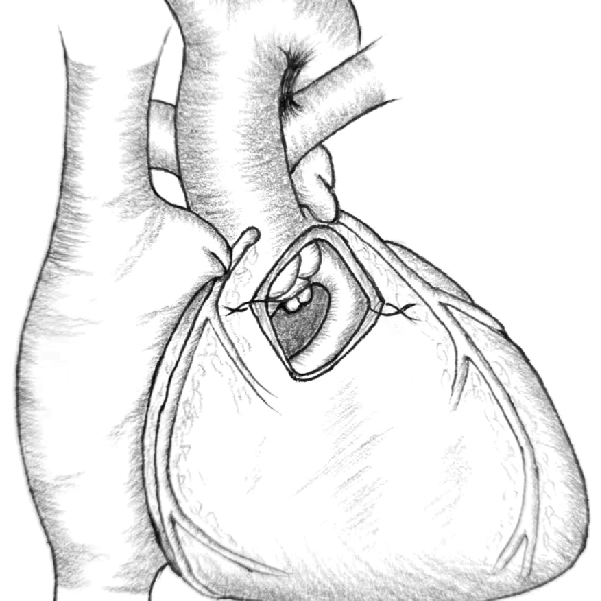

本例手术步骤:肺动脉根部离断肺动脉后,缝闭肺动脉近端。右心室无冠区做T形切口,经右心室切口,扩大室间隔缺损,缝合牛心包补片修建左室至主动脉的心内隧道。左心耳上缘与肺动脉切口下缘吻合,左心耳下缘缝合于右室切口上缘,形成肺动脉主干后壁,测量约18-20mm宽。取22#流出道单瓣补片,裁剪至合适大小,缝合至形成的肺动脉主干及右室流出道前壁,完成右室流出道及肺动脉重建。手术过程顺利,单瓣植入位置理想,术后超声见瓣叶开合正常,压差均在理想范围内,瓣膜微量返流。术中及术后患者生命体征平稳,无并发症发生。

右室T形切口 缝合左心耳重建肺动脉后壁